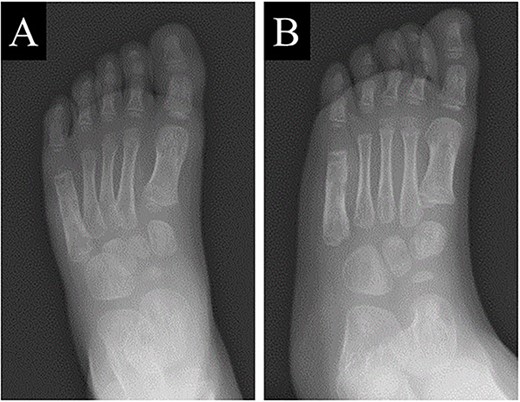

A 21-month-old Japanese female infant presented with a swollen mass on the dorsolateral aspect of the left foot. Her parents noticed the mass and brought the patient to our hospital. The patient had no past medical histories or complications prior to the occurrence. In addition, she received the BCG vaccine at the age of 4 months in Japan. At first visit to our hospital, physical examination revealed the ~3 × 3 cm mass was located on the dorsolateral aspect of the left foot and was hard accompanied by local heat (Fig. 1). Plain radiographs of the left foot showed a lytic lesion without periosteal reaction in the fifth metatarsal bone (Fig. 2). Magnetic resonance imaging (MRI) showed an isointense lesion on T1-weighted images and a hyperintense lesion on T2-weighted images around and within fifth metatarsal (Fig. 3). Gallium scintigraphy revealed intense uptake in the patient’s left foot (Fig. 4). In addition, laboratory examination was within normal. Based on medical history, clinical and imaging findings, we considered the possibility of neoplasia or osteomyelitis and performed an open debridement and biopsy of the lesion to make a diagnosis. The lesion was yellow and consisted of weak, adipose-like tissue that surrounded and continued into the inferior of the fifth metatarsal bone (Fig. 5). The lesion inside and outside the bone was resected as much as possible. Histopathologic examination of the lesion showed granulomatous inflammation including anaplastic giant cells, Langerhans-type giant cells and caseous necrosis (Fig. 6). Based on these results, TB or BCG osteomyelitis was considered as a diagnosis. The tuberculin test was positive, but the QuantiFERON TB test was negative. In addition, samples analyzed using polymerase chain reaction did not identify M. tuberculosis, but did identify the BCG Tokyo-172 strain. Per these findings, the patient was diagnosed with BCG osteomyelitis of the fifth metatarsal and oral treatment with anti-TB medicine including isoniazid (100 mg/day) and rifampicin (150 mg/day) was started. Clinical findings included reduction in swelling of the mass and gradual remodeling of the lytic lesion of the fifth metatarsal on plain radiographs (Fig. 7). However, 10 months after starting the anti-TB treatment, the mass recurred, and MRI revealed a residual high-intensity lesion around and inside the fifth metatarsal on T2-weighted fat-suppressed images (Fig. 8). It was determined that the lesion was difficult to control with anti-TB treatment alone, so an open debridement for the lesion was performed again. Histopathologic examination of the lesion revealed an epithelioid granuloma with necrosis. Therefore, the anti-TB treatment was continued. Six months after the second surgery, clinical and radiographic image findings showed complete improvement (Fig. 9). As a result, anti-TB treatment was ended. At the time of writing this report, 8 years after starting anti-TB treatment, there has been no recurrence.

At 6 months after the second surgery, image findings on plain radiographs completely improved on (A) anteroposterior and (B) oblique views.